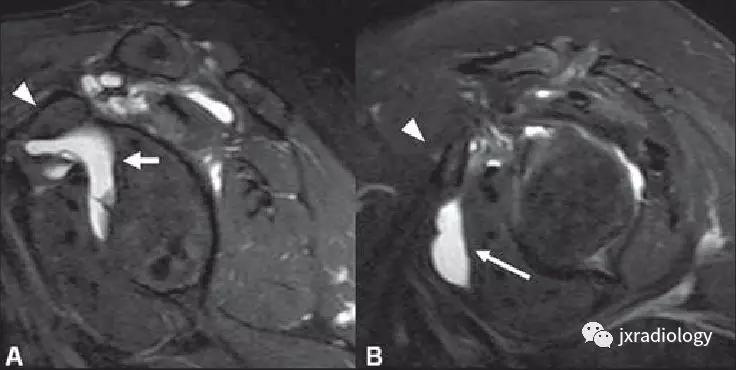

A图:(superior subscapularis recess):肩胛下肌上隐窝

B图:subcoracoid bursa:喙突下滑囊

箭头:subcoracoid bursa:喙突下滑囊积液

箭:退变和内侧脱位的肱二头肌长头肌腱